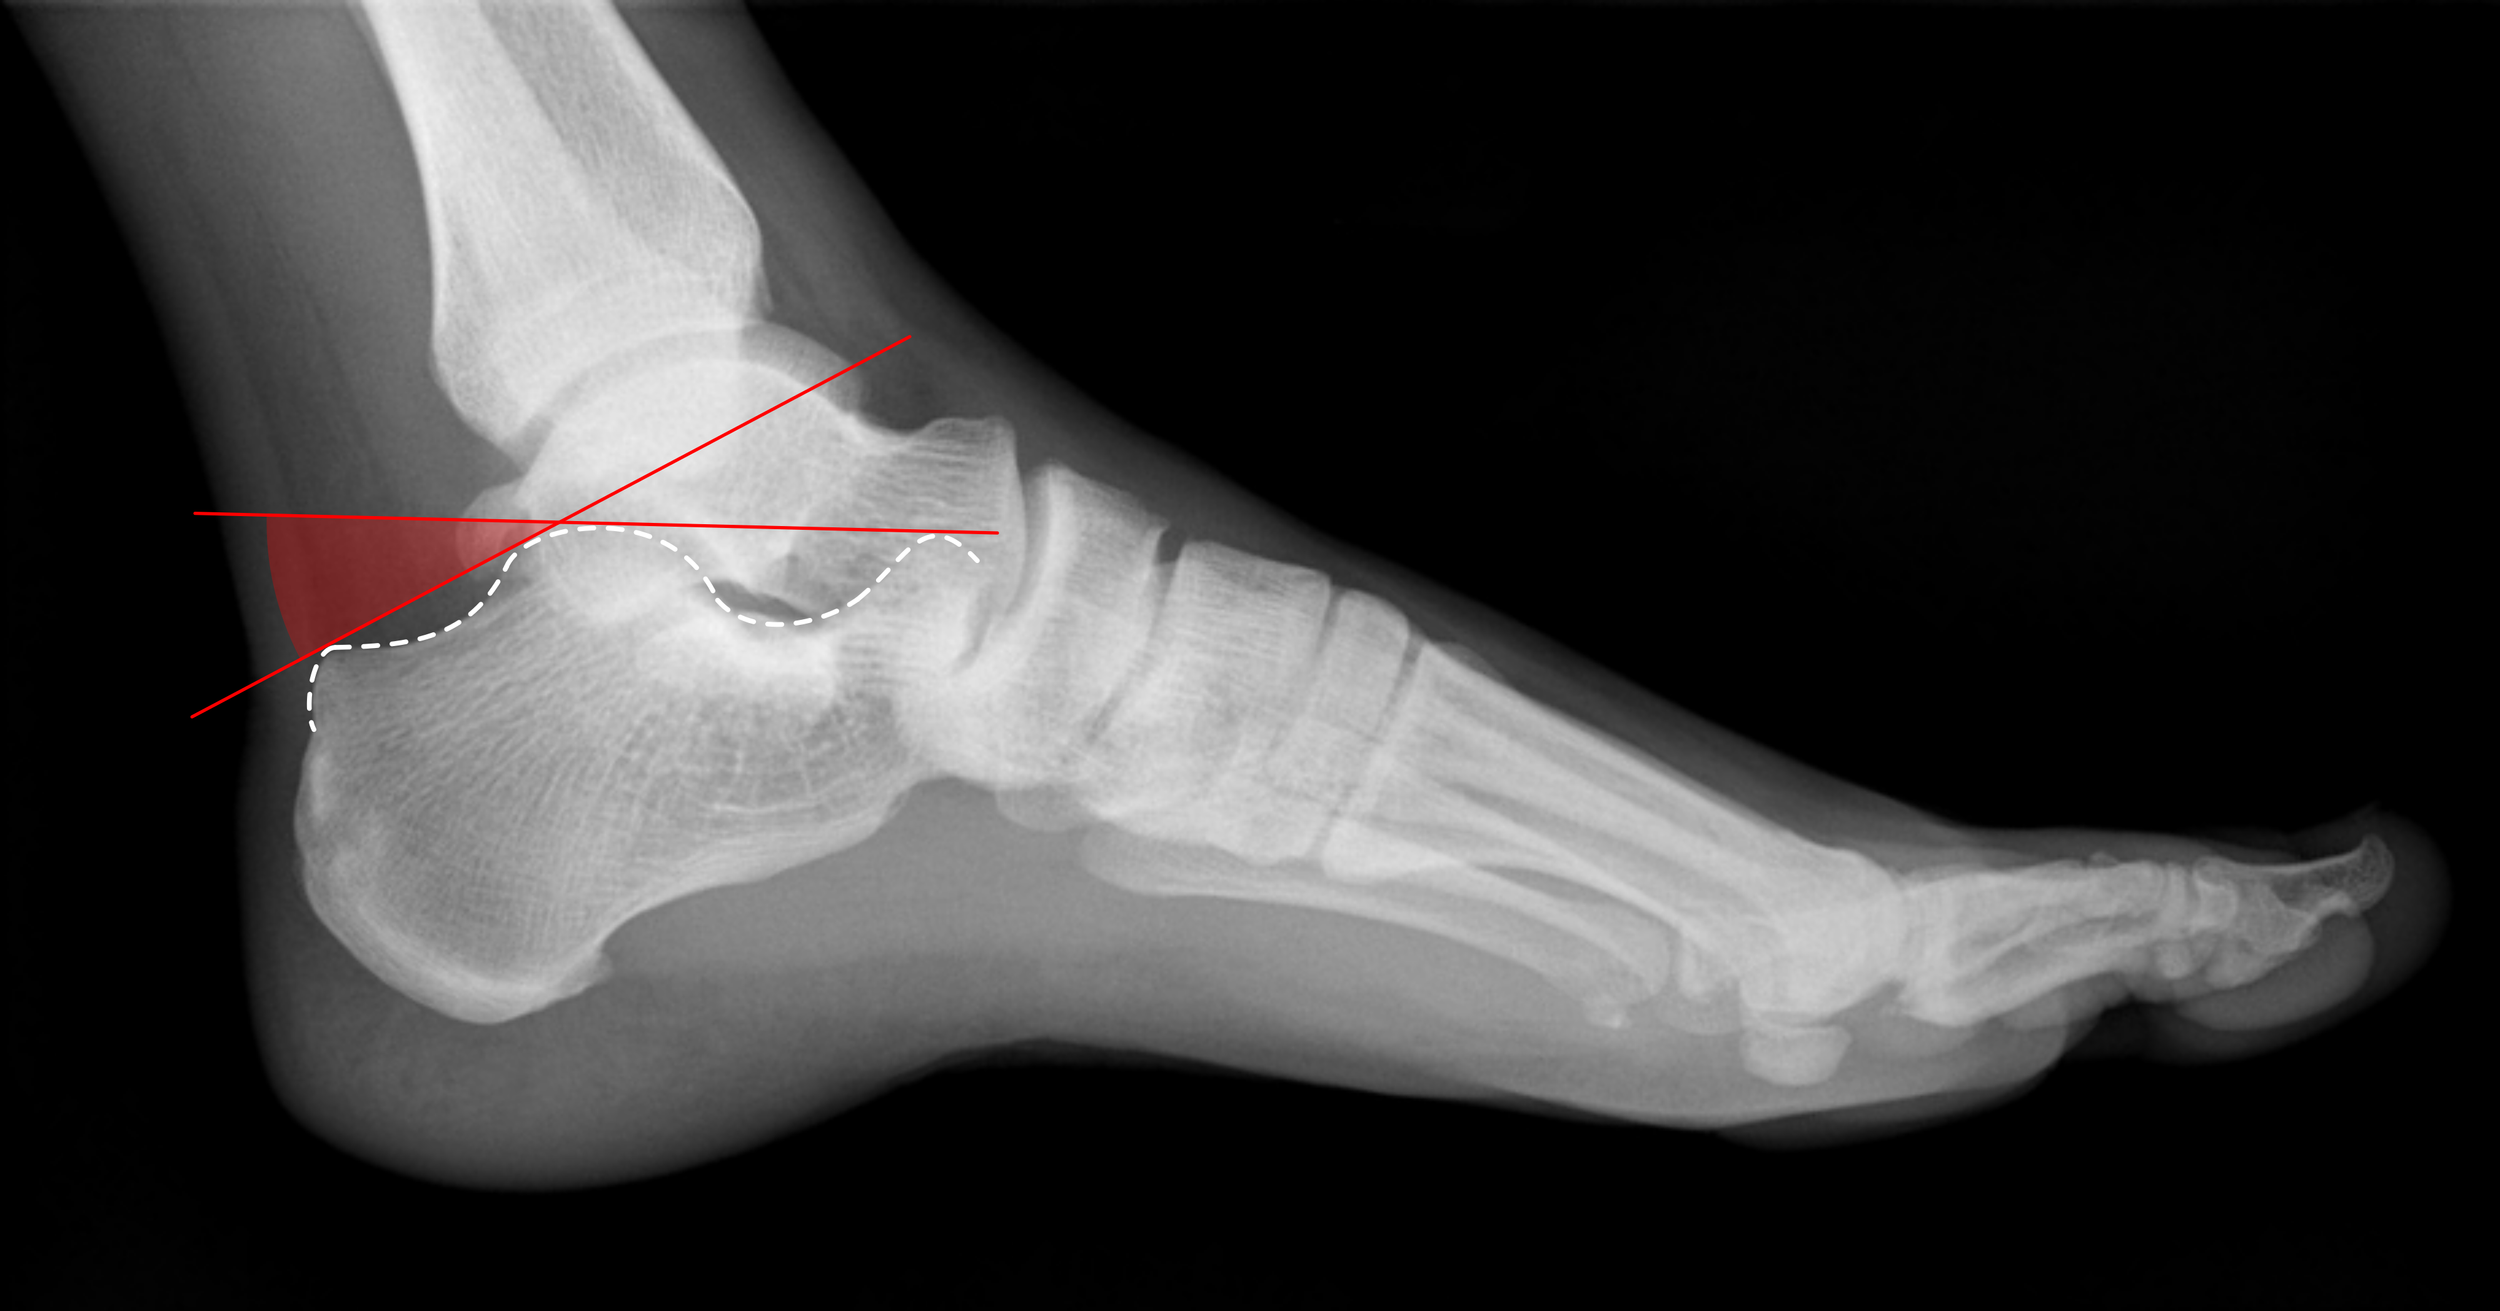

Angle of Bohler

• Line drawn from top of anterior calcaneus to top of posterior articular facet + Line drawn from calcaneal tuberosity to top of posterior articular facet = intersection is your angle

• Normal = 25-40 deg

• Decreased angle = Increased suspicion for displaced, intra-articular calcaneal fracture

• The more the angle is decreased = more severe injury

• The more the angle is restored to normal by treatment = better functional outcome

• Radiopaedia article

Case courtesy of Leonardo Lustosa, Radiopaedia.org, rID: 94702 (Bohler Angle)